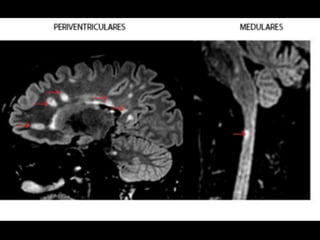

• Embora amplamente difundidas, certas áreas são

mais afetadas (>

sintomas)

– Região periventriculares

– Justacorticais

– infratentoriais

– Pedúnculos cerebelares

– Tronco encefálico

– Localização posterior ou lateral na Medula espinhal

• As lesões tendem a ser simétricas e têm

uma distribuição perivenosa (em torno de

pequenas veias e vênulas), contendo

linfócitos e macrófagos.

critérios

McDonald

(2017)

• disseminação

no

espaço

– RM

por

≥

1

lesões

hiperintensas

em

T2,

sintomá+cas

ou

assintomá+cas,

que

são

caracterís+cos

de

EM,

dois

mais

das

seguintes

quatro

áreas

do

sistema

nervoso

central:

• periventricular,

• cor+cal/justacor+cal,

infratentorial

e

medula

espinhal.